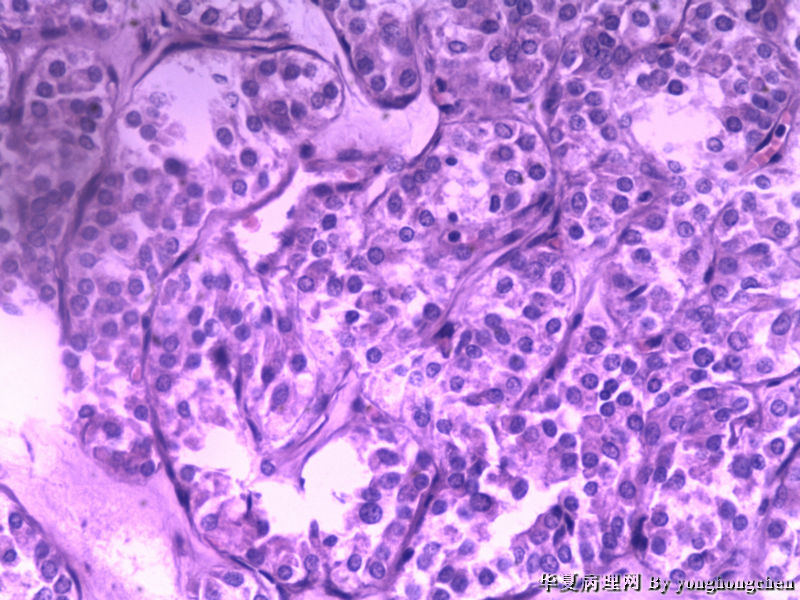

可不可能是嗜酸细胞腺瘤?

女,22岁,左侧甲状腺肿物6*4*2厘米,包膜完整,切面灰红,质软。

有些地方像甲状旁腺

不是甲状旁腺,是甲状腺内的肿块。

图二间质内似有玻璃样物质,染PAS,排除HTT。

注意观察包膜侵犯情况。

我看还像有甲状旁腺组织?